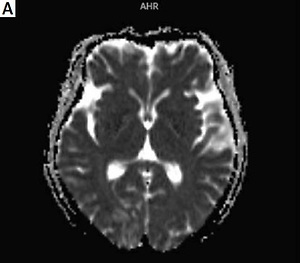

Scleroderma renal crisis with posterior reversible encephalopathy syndrome

Arch Med Sci 2023;19(2):536-538